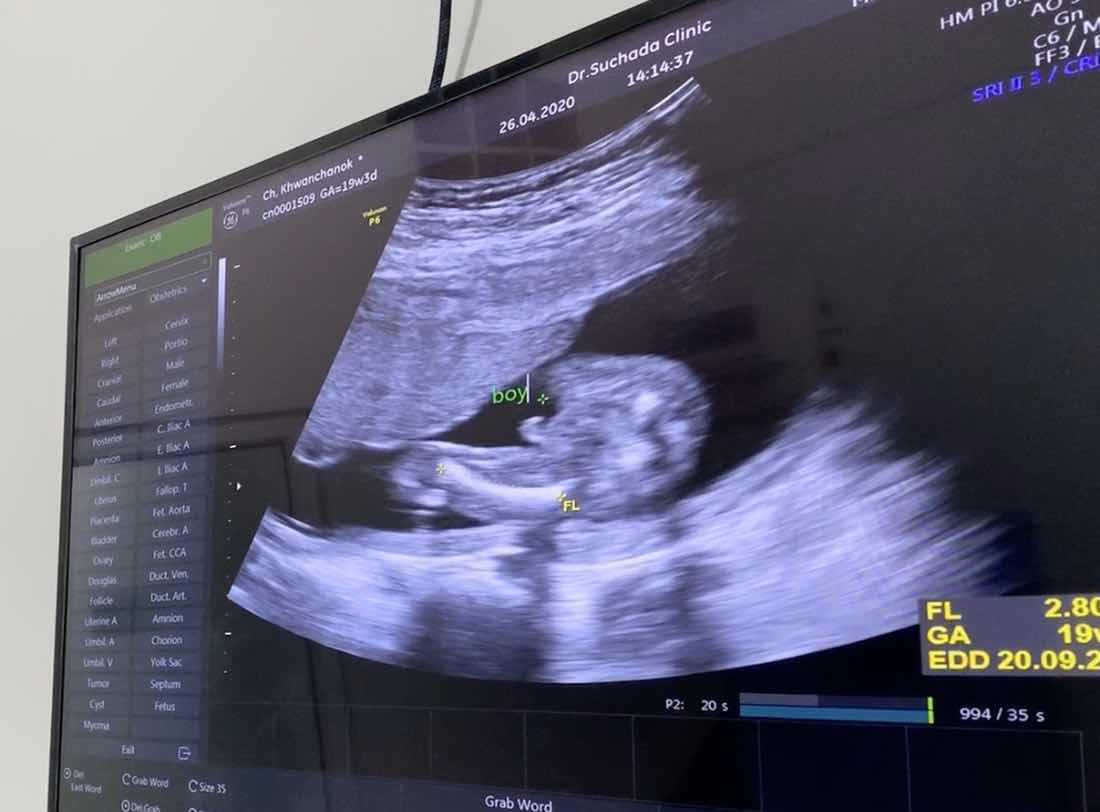

ในภาพเป็น ผช ใช่ไหมค่ะ พอดีหมอขอชัวร์ๆ เดือนหน้า เลยสอบถามแม่ๆ ที่มีประสบการณ์ลูกชาย หน่อยค่ะ ?ขอดูใบอัตตลาซาวเด็ก ผช . หน่อยจร้าาา? ถาพไม่ชัดเพราะถ่าย VDO มาจร้า ??

หมอบอกผู้ชายค่ะ

หมอบอก ผช. ค่ะ

ชัดเจนค่ะ😁